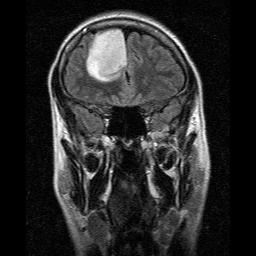

1974. március 5-én születtem, 34 éves múltam. 2008. október 14-én műtött dr. Czirják Sándor agydaganattal. A daganat a jobb homloklebenyem több mint egyharmadát foglalta el. A szövettan szerint oligodendroglióma grade II-es típusú volt a daganat. Aziránt érdeklődöm, hogy mennyi ideig normális a műtét utáni depresszió? Most már 34 nap eltelt, és én egyre nyomorultabbul érzem magam. Felváltva vagyok levert és őrjöngő. Egyszer nincs kedvem semmihez, iszonyú fáradt, kimerült, üres, energiátlan vagyok, állandóan csak aludnék és feküdnék, de nem lehet, mert el kell látnom a 15 hónapos kislányomat és a háztartást is. Az anyukám és a párom sajnos nem sokat segít benne, hogy hagyjanak pihenni. Amikor meg rám tör az ötperc, mindenkivel ordibálok, majd kiszakad a szívem a helyéből, felmegy a vérnyomásom, és azon járatom az agyam, hogyan tudnám minél előbb legyilkolni magam, mert már nagyon elegem van magamból. Nem akarom diagnosztizálni magam, de azt gondolom, depressziós vagyok. Ez normális agyműtét után? Végülis meg lett bolygatva az agyam, a biokémiai egyensúlya stb., talán ezért is... Nem tudom. Úgy érzem, teljesen rajtam kívül történnek a dolgok, nem én döntöm el, hogy most akkor nekiállok szomorkodni vagy dühöngeni, hanem csak megtörténik velem. Nem bírok relaxációs anyagokat hallgatni, mert ideges leszek tőlük... Mit tegyek, hogy ne menjek a környezetem, a szeretteim és a magam agyára?

Oligodendroglióma

Az oligodendroglióma az agydaganatok egyik típusa, idegszövet eredetű daganat. Általában középkorú embereknél jelentkezik, és többnyire lassan növekvő tumor. A grade 2 a daganat szövettani rosszindulatúságának mértékére utal, ez az érték közepesen rosszindulatú daganatot jelent.

Legsűrűbben 45-50 éves korban fordul elő. Szövettanilag jóindulatú daganatnak számít (rosszindulatú formája az oligodendroglioblastoma), ám gyakran beszűri a környezetét, emiatt teljes egészében nagyon ritkán távolítható el. Ebből következően kiújulása ugyancsak borítékolható, ám a klinikai gyakorlatban fellelhetők olyan esetek is, amikor többszöri operációval a betegnek 15-20 éves túlélést is tudtak biztosítani az orvosok.